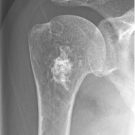

Stacy H. Leung, MD, MBA; Namita Bhardwaj, MD, MS, MPH; Ashley Echeta, MD; John C. Hagedorn, II, MD

A 79-year-old, right-handed woman presented to her primary care physician’s office with no prior hospitalizations for persistent right arm pain associated with a right antecubital mass.